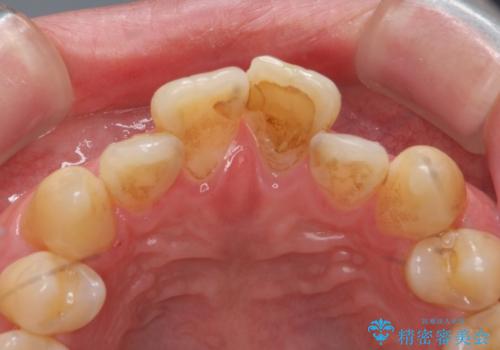

- 前歯の突出を主訴に来院。

全体矯正を行うとなると健康な歯を4本抜歯することになるため、歯は抜かず上だけの部分矯正で最小限で前歯を整えることにしました。

前歯は少し細く削って前に出ないように整えました。

左上の1番目の前歯は神経を取ってある歯でした。今後変色もすすんでいくため、治療のやり直しを行いセラミックでかぶせました。

左上の2番目の前歯は虫歯治療を行い、神経治療まで行っています。